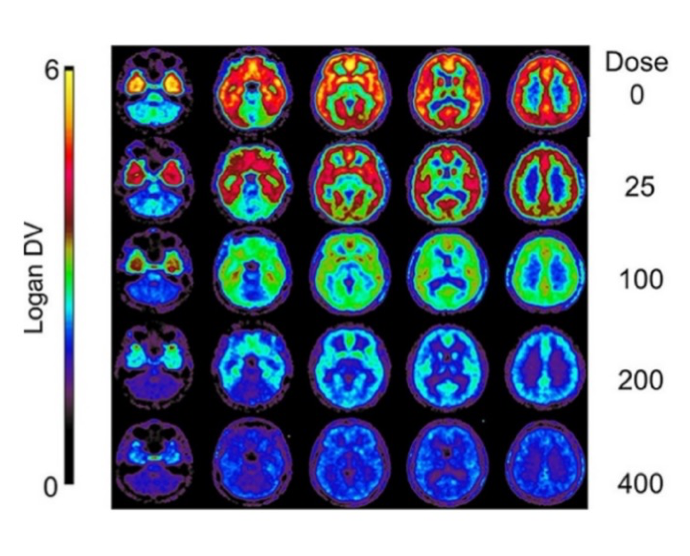

pmod’s tools provide comprehensive workflows for post-processing and quantification of imaging data for fundamental oncology research, development of radiotracers and theranostics, and in clinical research studies. Imaging scientists can trust pmod to reproducibly read their data, interpret the meta-data/units and help users calculate statistics such as SUV for their studies and publications.

For treatment evaluation and theranostic development

• Full access to metadata – ensure accurate calculation of Standard Uptake Value and other key statistics

• Flexible switching between 3D and 4D datasets – direct output of time activity curves